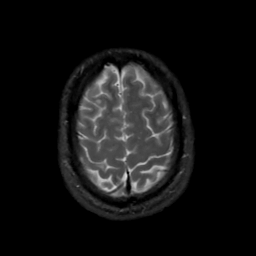

MR Study #3, February 24, 1991 -- Slice #42